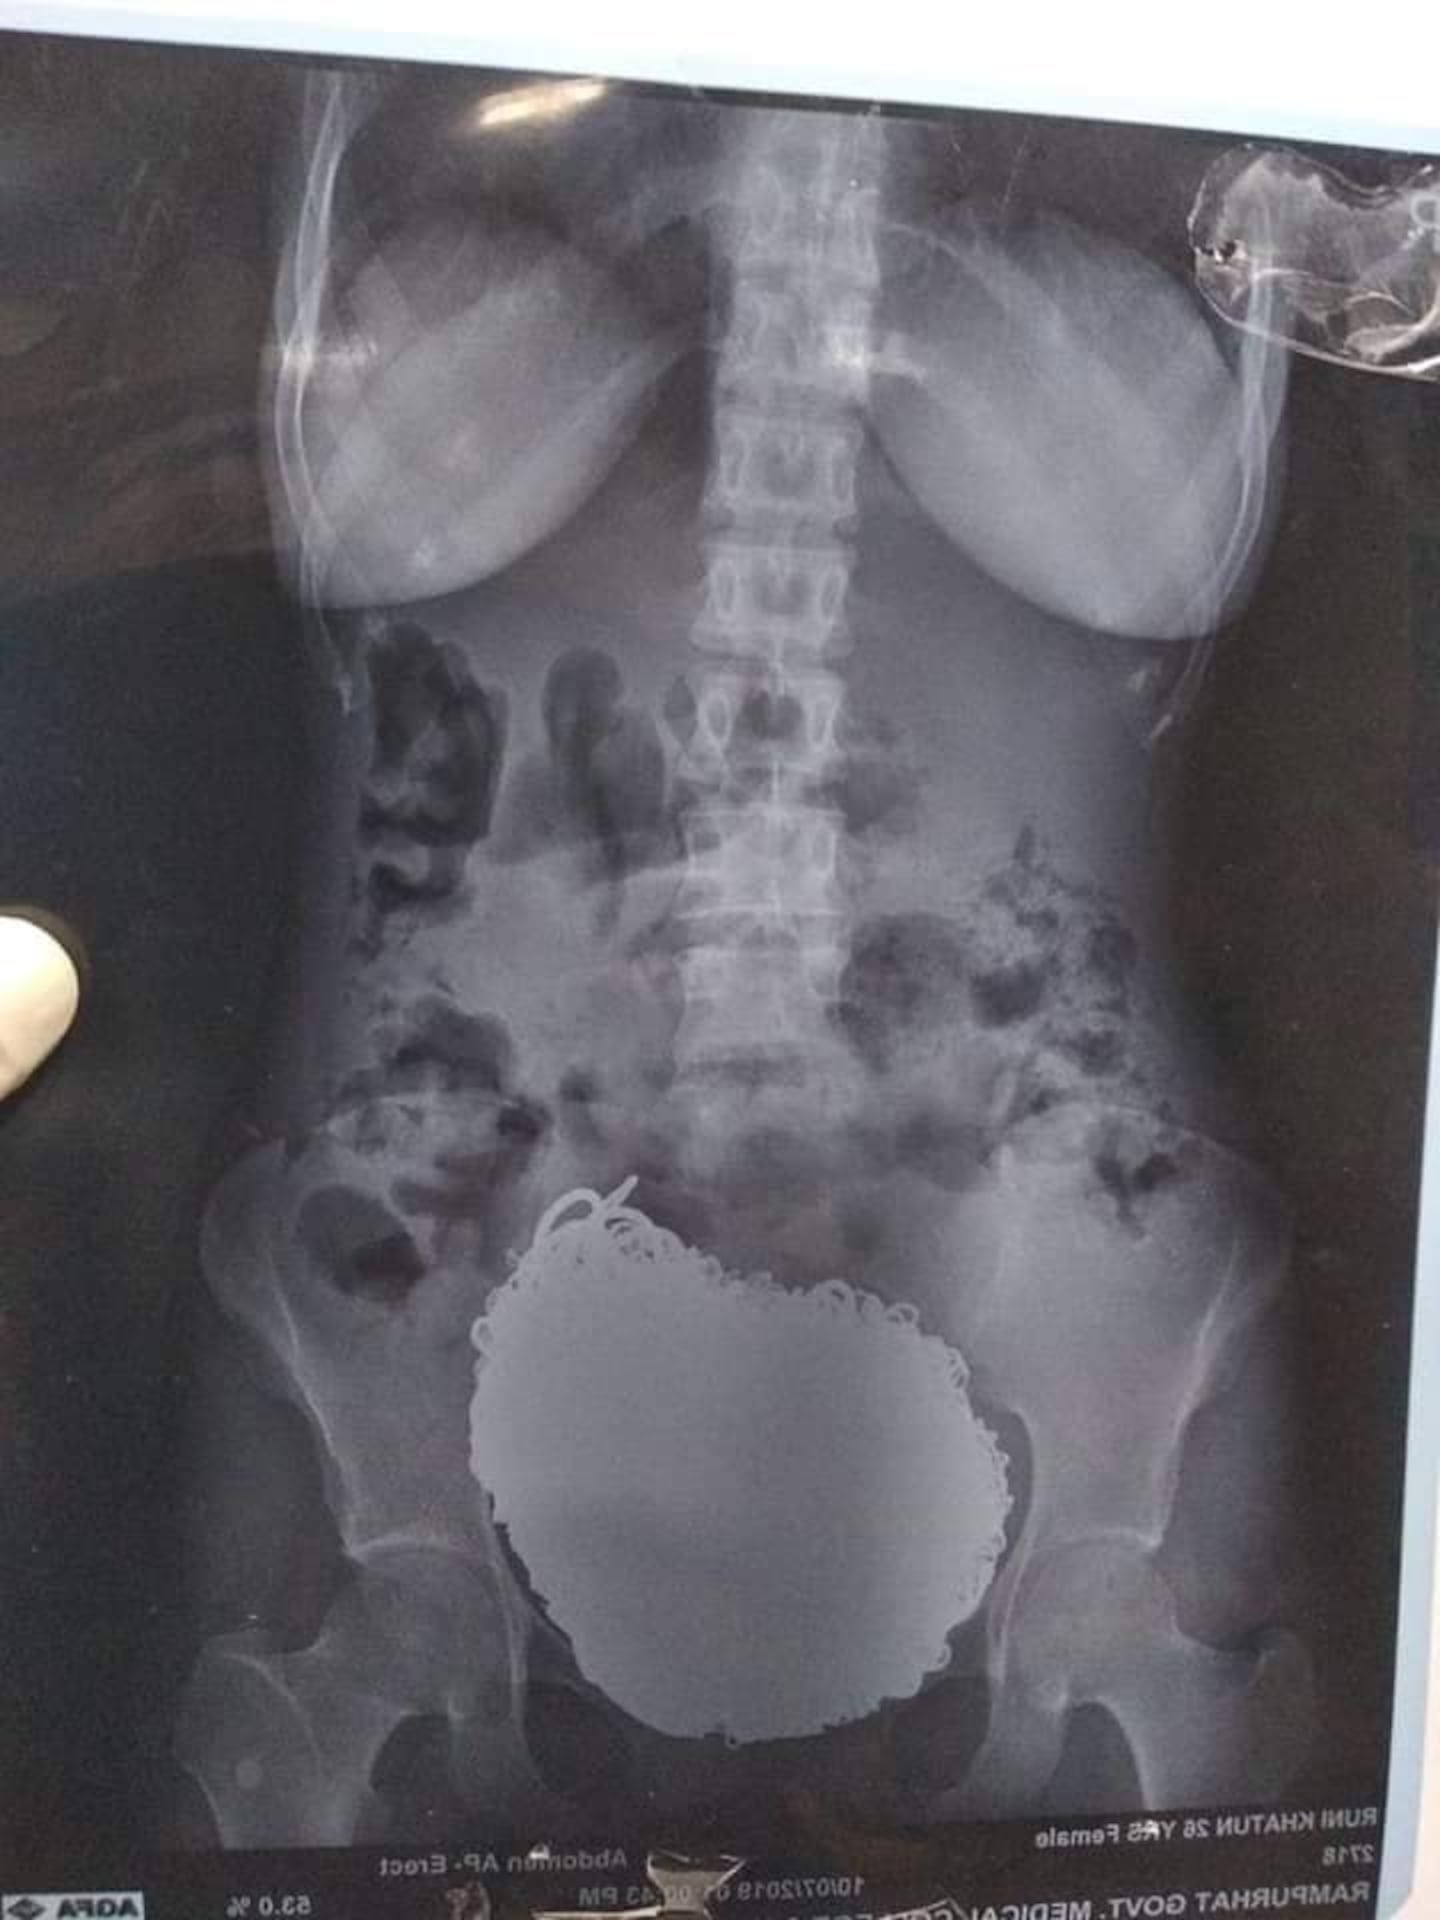

X-rays shared on the hospital's Facebook page, show the mass of metal in the the woman's stomach, but doctors said they did not imagine the amount of treasure that was inside.

The operation lasted for a little over an hour and surgeons reported removing chains, nose rings, earrings, trinkets, bangles, 90 coins and even a wristwatch.

The Facebook page says the contents weighed nearly 68 kg which is about 149 pounds!